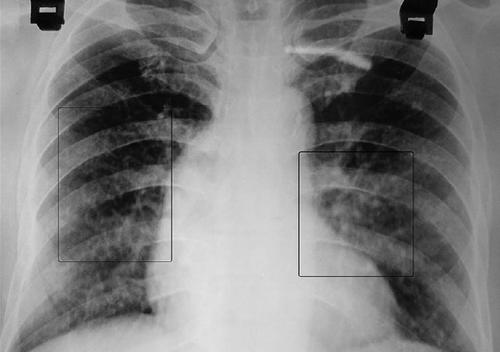

肺部疾病有哪些症状

据研究发现,现在生活中有许多人都会患上肺部疾病,肺部疾病的发病率在逐步的上升,那...